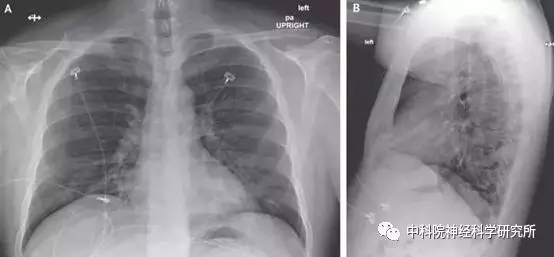

2020年2月1日,《新英格兰医学杂志》报道了美国首例确诊新冠肺炎患者被成功治愈的病例。

患者是一名35岁的男性,1月19日从武汉回来后因咳嗽和发烧遂到华盛顿州斯诺霍米什县的诊所就诊。

之后美国疾病防控中心通过实时逆转录聚合酶链式反应 (RT-PCR)的方法确诊此人患有新冠肺炎。

医院前期主要对患者进行支持性治疗,但不见好转。在住院第7日晚上,医师将一种试验性抗病毒药进行了特许用药。

在用药的第二天晚上,患者临床症状得到缓解。截止到1月30日,患者除咳嗽改善比较缓慢外,其他临床症状均已消退。